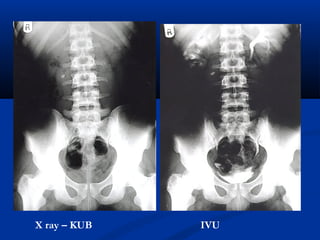

X ray – KUB IVU

X ray –KUB IVU